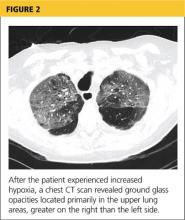

At pulmonology two months later, she had a chest x-ray (see Figure 3) and pulmonary function tests (PFTs). The patient reported feeling progressively better in the past month. Her dyspnea on exertion had improved, and she did not require supplemental oxygen anymore. She stopped smoking cigarettes.

The patient continued to use fluticasone/salmeterol but stopped tiotropium bromide. On physical exam, her O2 saturation was 95% on room air, heart rhythm and rate were regular, and her lungs revealed very minimal crackles at the right base but were otherwise clear.

The plan specified continuing the prednisone taper. The patient was asked to call the office if she had any worsening shortness of breath, cough, and sputum production. She was also encouraged to continue refraining from smoking cigarettes. This patient had done very well, with near complete resolution of symptoms and a clear chest x-ray.